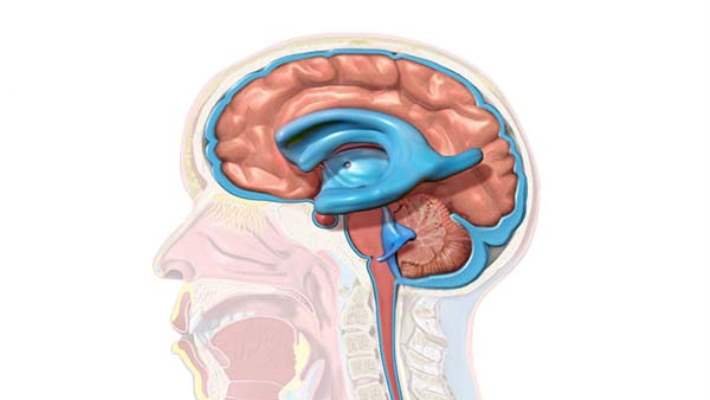

Hidrosefali, beyin omurilik sıvısının tıkanıklığı, emilim dengesinin bozulması nedeniyle... Devamı